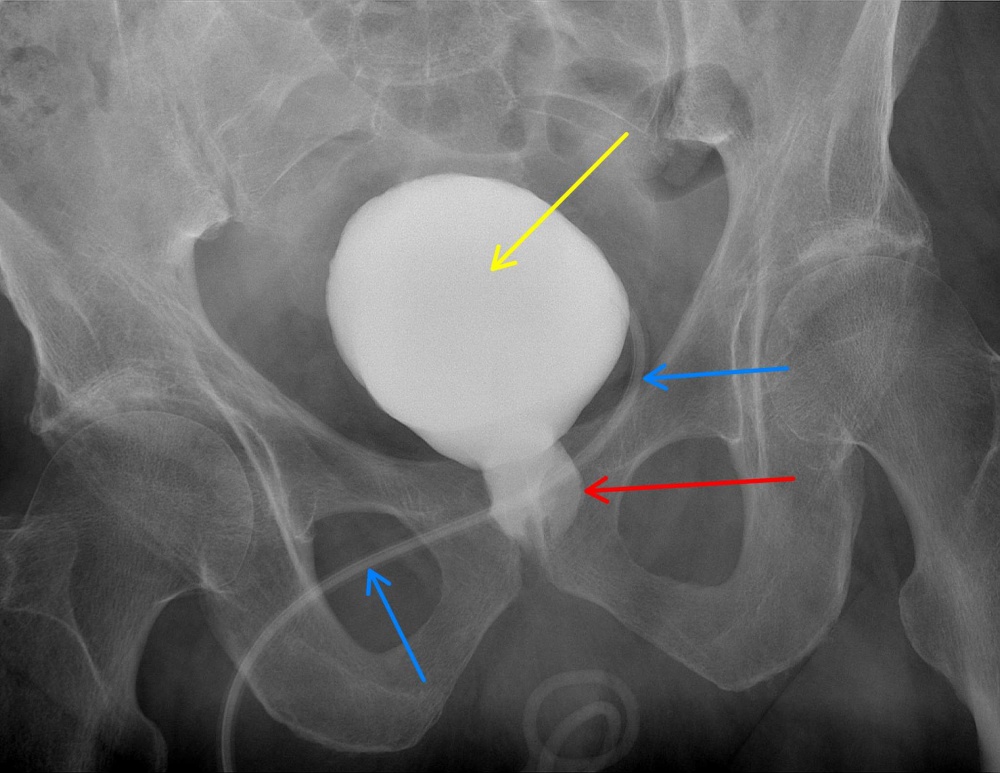

Enukleationshöhle/ Prostataloge; gelber Pfeil: Blase; blauer Peil:

suprapubischer Blasenkatheter (Epizystotomie)

Routinemäßig erfolgte die Einlage einer Char. 12 Epizystostomie[2], transurethral wurde ein Char. 24 Spülkatheter eingelegt und mit 130 ml in der Enukleationshöhle/Prostataloge geblockt. Die Blase wurde anschließend zweischichtig verschlossen.

Nach Entlassung aus unserer stationären Behandlung unterzog sich der Patient einer Rehabilitationsmaßnahme und stellte sich schlussendlich 4 Monate nach dem Eingriff zur abschließenden Kontrolluntersuchung vor. Die zu diesem Zeitpunkt angefertigte Zystographie zeigte eine mittlerweile deutlich geschrumpfte Enukleationshöhle/Prostataloge (Vorblase). Der Patient konnte seine Blase spontan und restharnfrei entleeren – eine Inkontinenz bestand nicht. Aufgrund dieses sehr erfreulichen Befundes konnte die Epizystostomie entfernt werden.